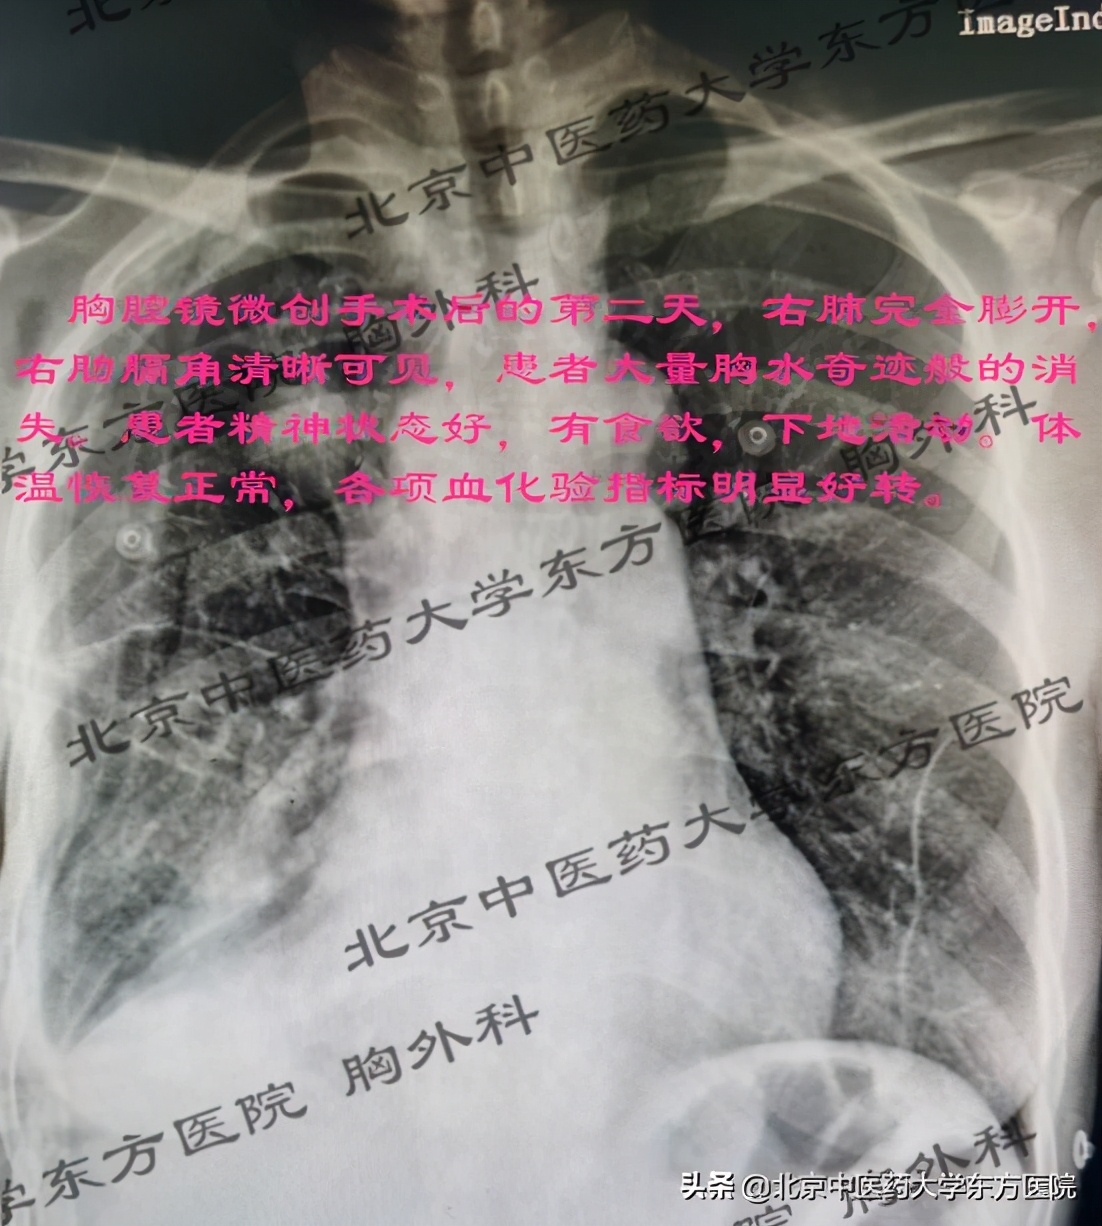

胸腔镜微创手术-术中见:(如图)